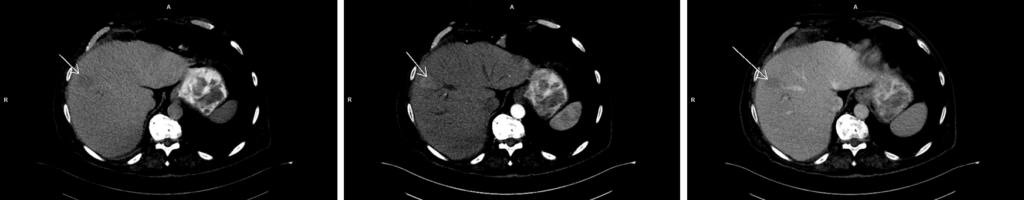

Figura 1: axial CT nativ, timp arterial și timp venos